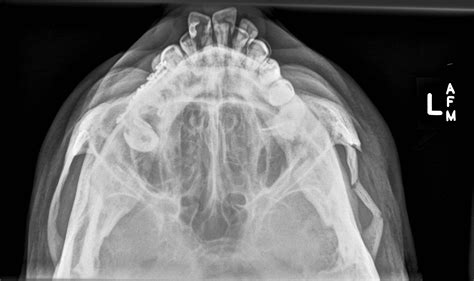

In the realm of medical diagnostics, the Smv Zygomatic Arches Xray plays a crucial role in assessing the structure and integrity of the zygomatic arches, which are the bony structures that form the prominence of the cheeks. This diagnostic tool is essential for evaluating various conditions, including fractures, tumors, and developmental anomalies. Understanding the significance and procedure of a Smv Zygomatic Arches Xray can provide valuable insights into its importance in modern medical practice.

The zygomatic arches are part of the facial skeleton and are formed by the zygomatic bones. These bones connect to the temporal bones and the maxilla, creating a framework that supports the facial muscles and soft tissues. The zygomatic arches are critical for facial aesthetics and function, making their assessment through imaging techniques like the Smv Zygomatic Arches Xray indispensable.

The Smv Zygomatic Arches Xray is a specialized radiographic technique used to visualize the zygomatic arches and surrounding structures. This imaging method is particularly useful in the following scenarios:

• Trauma Assessment: In cases of facial trauma, such as fractures resulting from accidents or assaults, the Smv Zygomatic Arches Xray helps identify the extent and location of fractures.

• Tumor Detection: It aids in the detection and evaluation of tumors or other masses affecting the zygomatic arches.

• Developmental Anomalies: This Xray can reveal congenital anomalies or developmental issues that affect the zygomatic arches.

• Pre-Surgical Planning: Surgeons use the Smv Zygomatic Arches Xray to plan reconstructive or corrective surgeries involving the zygomatic arches.

Interpreting the results of a Smv Zygomatic Arches Xray requires expertise in radiology. The radiologist looks for various indicators, including:

• Fractures: Visible breaks or displacements in the zygomatic arches.

• Tumors: Abnormal masses or growths that may affect the bone structure.

• Anomalies: Congenital or developmental issues that alter the normal anatomy of the zygomatic arches.

• Soft Tissue Involvement: Any signs of soft tissue damage or inflammation that may be associated with the zygomatic arches.